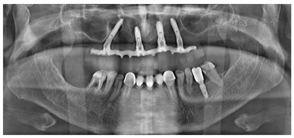

(1)种植一期手术:①阿替卡因肾上腺素注射液局麻下拔除上颌余留牙。②沿16-26区域牙槽嵴顶全层翻瓣,清除拔牙窝内炎性肉芽组织,平整牙槽嵴顶。③分别于12、22、25区定点,逐级备洞,12、22植入Nobel Speedy 4.0 mm×13 mm种植体;25近中倾斜植入Nobel Speedy 4.0 mm×15 mm种植体;④超声骨刀于13、14、15牙槽嵴顶8 mm处行唇、颊侧骨壁近远中向开窗,开窗面积约15 mm×8 mm,剥离上颌窦底黏膜后,15区定点,推开上颌窦底黏膜,近中倾斜备洞直达鼻底,倾斜植入Nobel speedy 4.0×18 mm种植体。⑤4颗种植体初期稳定性均达到35NCm,15颊侧骨开窗区种植体表面覆盖浓缩生长因子(Concentrated growth factor, CGF)(视频4)。⑥拔除18,12旋入RP17°3 mm复合基台,22旋入RP17°4 mm复合基台,15、25分别旋入RP 30°5 mm复合基台,修整牙龈组织,黏膜瓣复位、缝合创口,拍摄曲面体层片(图3)。

(2)即刻修复:制取上下颌硅橡胶印模,利用术前可摘局部义齿转移颌位关系,制作丙烯酸树脂临时固定义齿,咬合关系恢复至第二前磨牙,调整咬合。口内固定修复螺丝加力至15N.CM,牙龈硅橡胶封闭螺丝孔,拍摄曲面体层片(图4,图5)。

面像;E:佩戴后曲面体层片;F:戴牙后根尖片(3)制作终义齿:种植一期手术6个月后,制作钛支架丙烯酸树脂固定义齿,完成终义齿固定修复。

治疗结果:上颌即刻固定义齿试戴,义齿被动就位顺利,咬合关系恢复至第二前磨牙,义齿螺丝加力至15Ncm。检查患者前牙区覆

覆盖关系恢复正常,唇侧丰满度良好,双侧后牙区咬合关系稳定(图5,图6),患者满意。

即刻修复6个月后佩戴上颌终义齿,咬合关系恢复至第一磨牙,4颗种植体螺丝被动就位后分别加力至15Ncm。口内检查:中线、义齿边缘交界线、义齿切缘曲线、

平面、覆

覆盖关系、双侧磨牙咬合关系均良好(图7,图8,图9)。